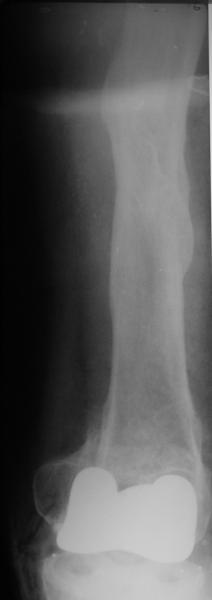

Глубокоуважаемые коллеги, Мужчина 41 года поступил с повторным (предыдущий в 2001 г.) переломом (3-недельной давности) над протезом коленного сустава.

В 1994 множественная травма, в том числе открытый перелом надколенника, осложнившийся гнойным артритом, и на этой же стороне перелом диафиза бедра (лечили в аппарате). В 1998 г. выполнено эндопротезирование коленного сустава. Предыдущий перелом (3 года назад) лечили консервативно, сросся при неустраненном смещении дистального блока бедра кзади ~ на 1 см. Амплитуда движений в коленном суставе перед последним переломом была ~90 градусов. Ходил без дополнительной опоры. Снимки в приложении. Какие будут предложения по поводу оперативного лечения в нынешней ситуации? У нас споры между ретро- и антеградным закрытым интрамедуллярным остеосинтезом.

A male 41 years old transferred to our unit with 3 week old femoral fracture near the knee prosthesis after a mimimal fall. In 1994 he sustained multiple injury with open patella fracture (complicated with septic arthritis), and ipsilateral femoral shaft fracture treated by ex-fix. TKA performed in 1998. In 2001 he got a periprosthetic fracture which was treated nonoperatively and healed with ~1 cm dorsal displacement of the distal femoral block. Knee ROM prior the recent injury was about 90-95 degrees. He didn't use walking aid. Images attached. I request your suggestions regarding surgical options in the situation? We mostly discuss ante- vs retrograde closed nailing.